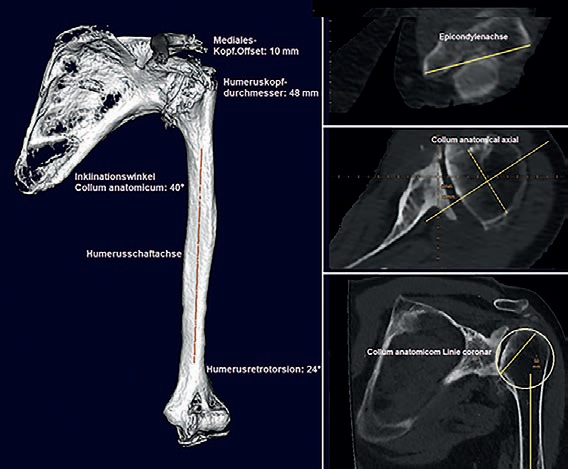

schneller. Ich brauche bspw. zwischen 5 und 10 Minuten für eine normale Schulterplanung. Für eine 3D-Planung

mit einer 3D-Gelenkrekonstruktion inklusive animierter 3D-ROM-Analyse und Betrachtung des Gelenkes aus verschiedenen

Blickwinkeln, so wie es aktuell mit der Software mediCAD® Shoulder 3D ermöglicht wird, brauche ich derzeit noch

Ich versuche bei jeder anstehenden OP mindestens eine digitale 2D-Planung, idealer Weise sogar eine 3D-Planung zu

machen. 3D-Planungen basieren aber auf CT-Bildern, und leider habe ich nicht immer ein geeignetes CT in der entsprechenden

Dünnschicht-Auflösung und Abmessung (ganzes Schulterblatt und Epicondylen ) zur Verfügung, denn viele Patienten

haben nur ein MRT dabei, bei dem meist nicht die eigentlich erforderlichen Endpunkte der betroffenen Knochen

abbgebildet sind und gehen davon aus, dass dies ausreichend sei. Eine digitale 2D-Planung ist aber auch anhand eines

MRT in Annäherung möglich, allerdings mit deutlich eingeschränkter Aussage gegenüber der 3D Planung mit reproduzierbaren

Referenzebenen in den Schulterblattebenen und Humerusachsen.

Deswegen bin ich gerade dabei mit unseren ortsansässigen Radiologen ein mediCAD® CT-Protokoll zu erarbeiten und

dabei die Vorteile der 3D-Planung mit Bestimmen auch der Humerus-Retrotorsion durch Erfassen der Epicondylenachse